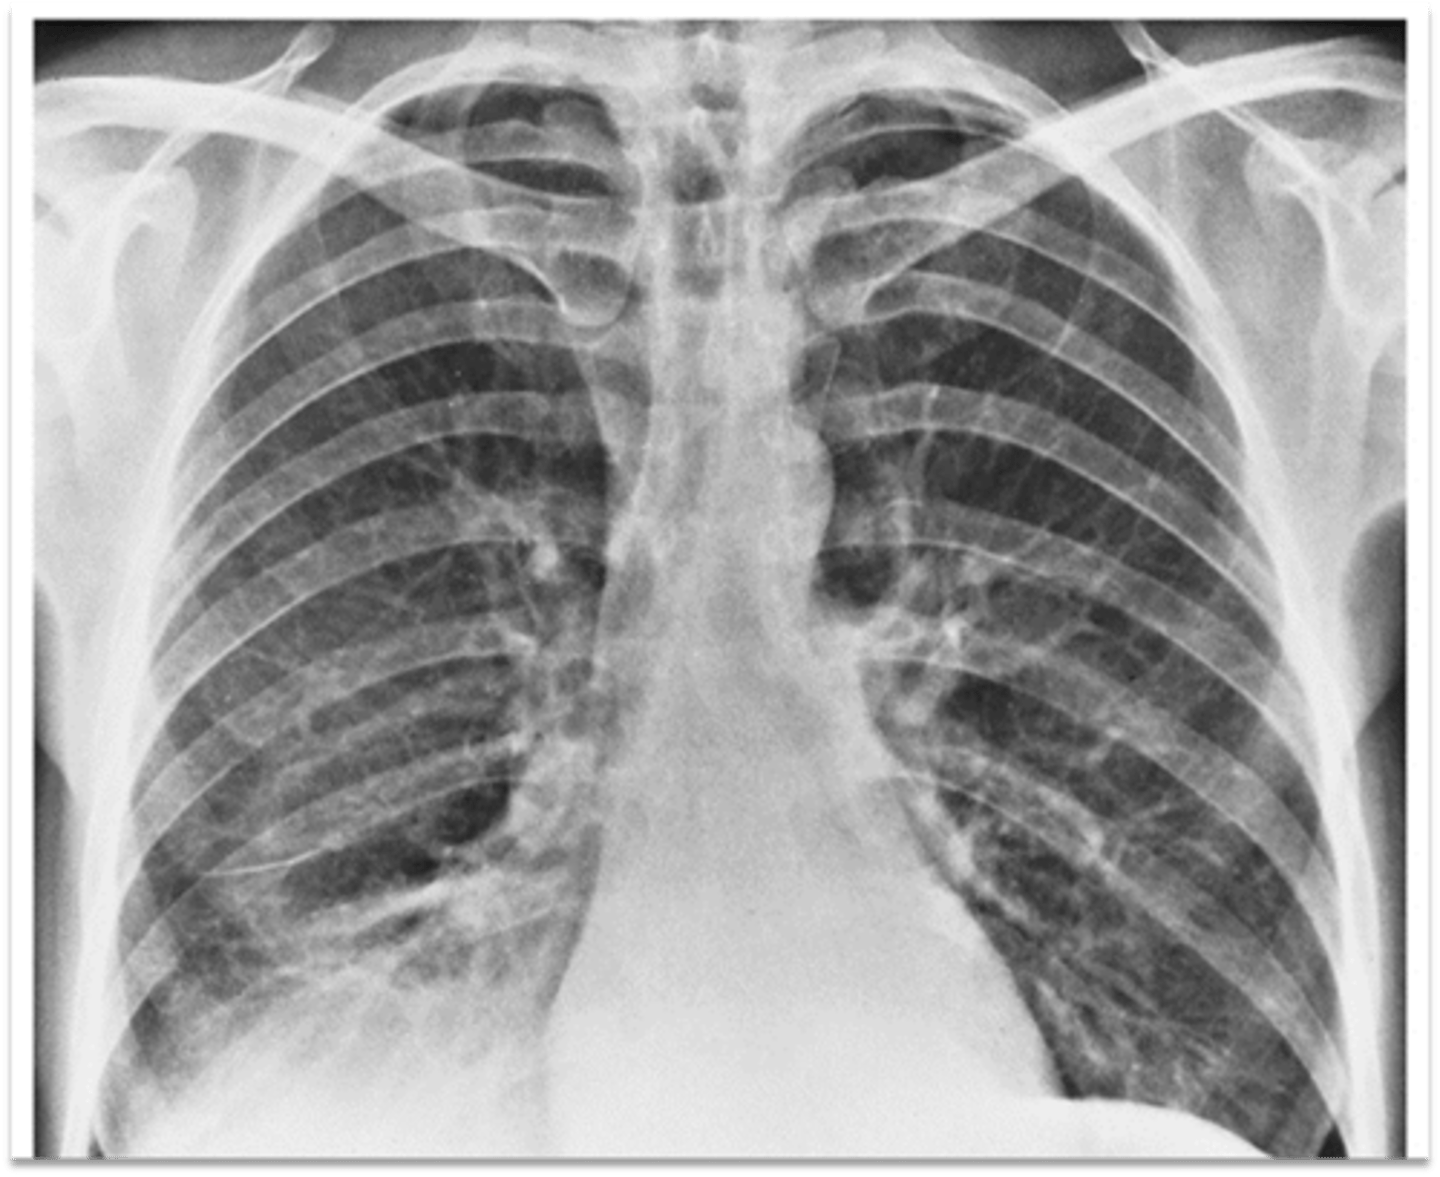

PA view (heart is normal size, patient is standing)

Which view is this?

AP view (heart looks bigger, slightly blurrier ribs, bedbound patients)

Which view is this?